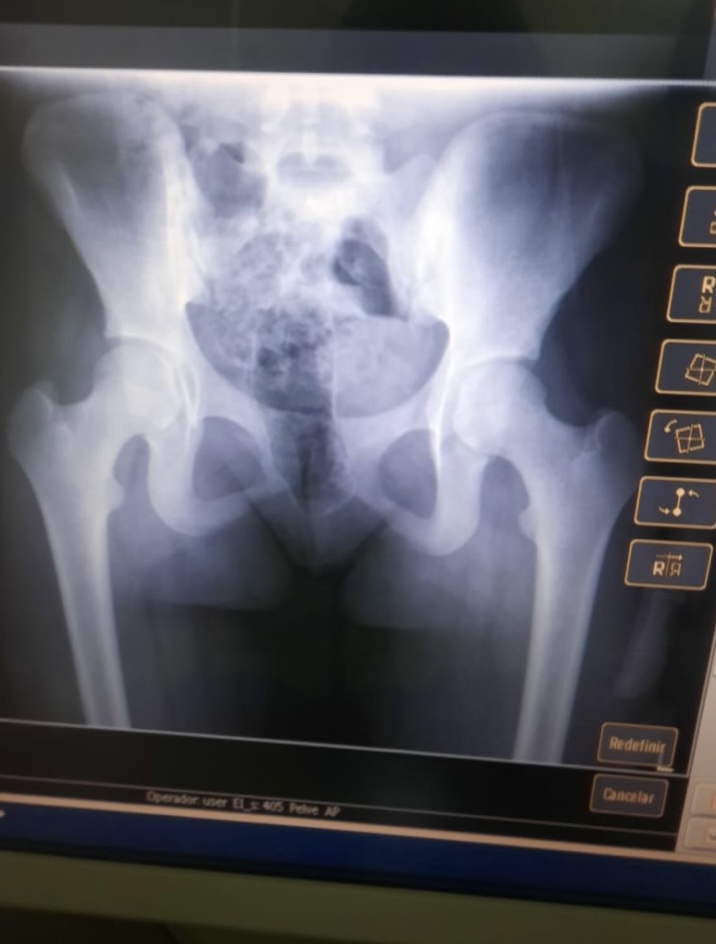

A prisão aconteceu durante uma visita, quando a mulher foi revistada pelas Policiais Penais e ao ser feito o scanner corporal foi detectado o entorpecente.